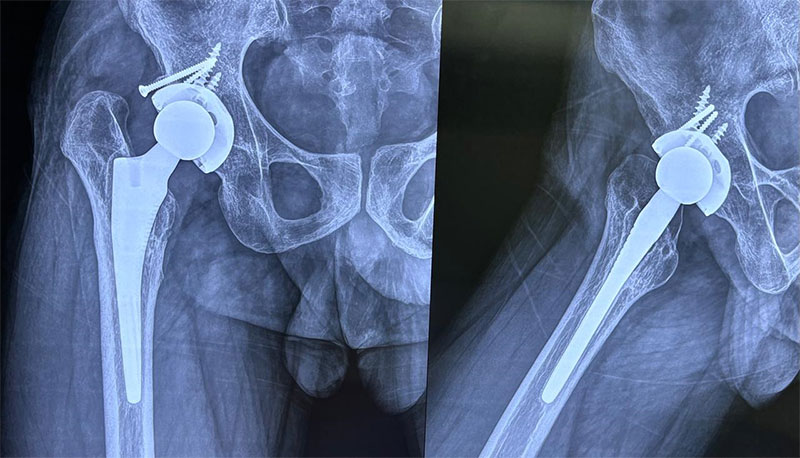

A 32-year-old male with a 7-year history of hip osteoarthritis underwent total hip replacement in 2018, with reconstruction of a false acetabulum using bone graft and screws. A recent X-ray shows a well-fixed implant in good alignment, and the patient reports pain-free walking with a good range of motion.